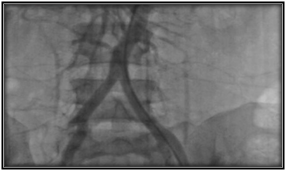

Transthoracic echocardiogram was performed in which trivalva aortic valve was observed with limited coaptation of the cusps that produces severe regurgitation, vena contracta of 6 mm, EROA of 0.5 cm2, aortic root of 36 mm, ascending aorta 35 mm, LVED 51mm, LVEF 59%. (Figure 2 & Figure 3) Severe aortic regurgitation was diagnosed, with Takayasu arteritis as probable etiology. Thoracic angiotomography and angiography were performed, showing areas of stenosis in the left carotid and the left subclavian artery. (Figure 4–7) The final diagnosis was severe aortic insufficiency secondary to dilation of the aortic root due to Takayasu's arteritis by Ishikawa criteria. Treatment with aortic valve replacement with mechanical prosthesis was decided.

Figure 6-8 Angiotomography.